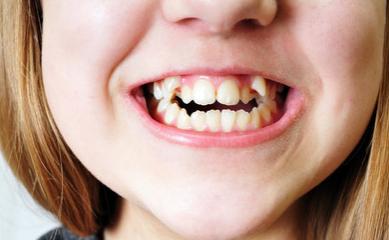

2、乳牙滞留或掉太快、磨损不够

这种情况可能会影响恒牙的发育和位置;

如出现双排牙,通过及时拔牙即可恢复到健康的状态;乳牙早失一旦发生,也可以通过检查来做间隙保持;龋齿等口腔问题更要及时处理。